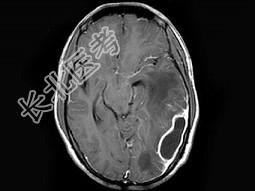

- 单项选择题男,30岁, 寒战,高热伴头痛, 呕吐10天,头颅MRI平扫及增强扫描见颅内不规则环形强化, 应诊断为 ( )

A、化脓性脑膜脑炎并脑脓肿形成

B、结核性脑膜脑炎并结核瘤形成

C、脑膜及颅内转移瘤

D、星形细胞瘤

E、未见异常